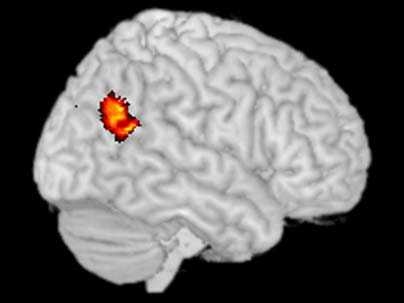

This brain scan, taken with functional magnetic resonance imaging, shows an area of the brain known as the temporoparietal junction (TPJ) lit up.  MIT neuroscientist Rebecca Saxe has shown that the TPJ is active when people think about other people's thoughts.

Using fMRI, she has identified an area of the brain (the temporoparietal junction) that lights up when people think about other people's thoughts, something we do often as we try to figure out why others behave as they do.